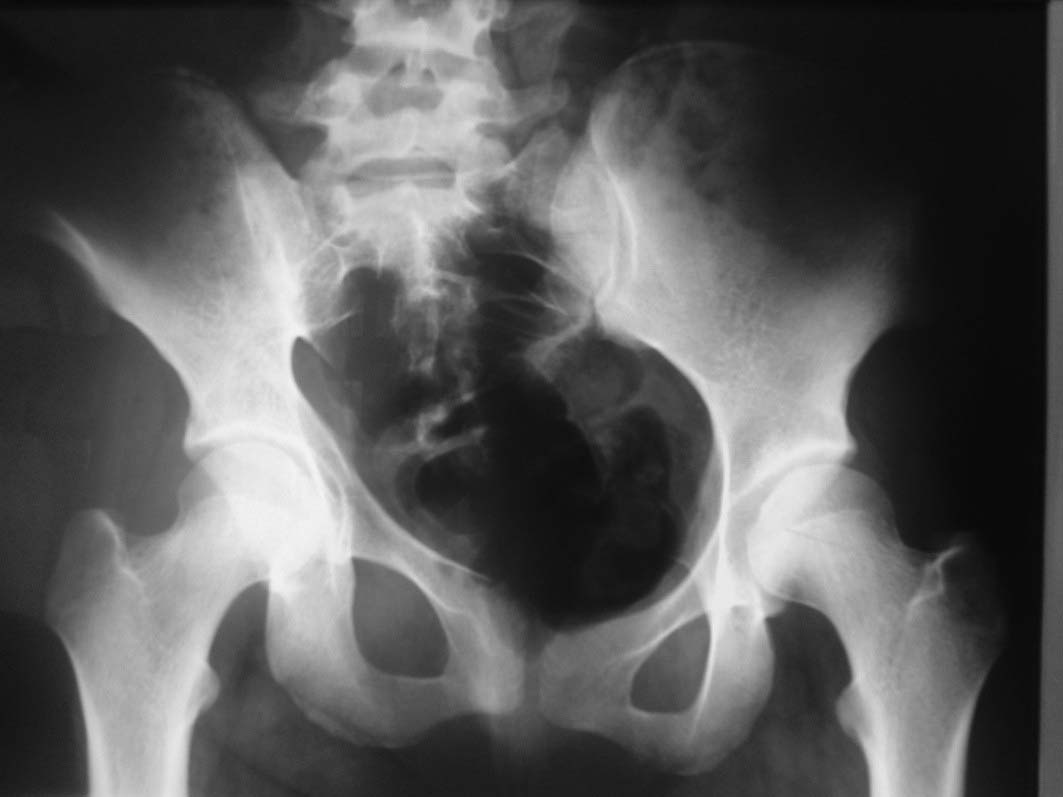

Здравствуйте.Помогите с диагнозом и тактикой лечения.

Больная 15 лет. Жалобы: на укорочение правой нижней конечности, хромоту. Анамнез: Со слов

болеет с детства, травму отрицает. Ранее за медицинской помощью не обращалась. Последние 2

года отмечает резкое укорочение конечности. Локально: При осмотре отмечается умеренное

искривление позвоночника во фронтальной плоскости, умеренная асимметрия лопаток и

надплечий. Скошенность таза. Отмечается укорочение правой нижней конечности на 3 см.

Движения в тазобедренном и коленном суставах в полном объеме. Нейрососудистых нарушений в

периферических отделах нет.